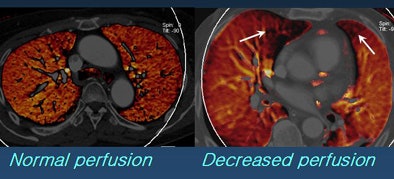

![]() |

| Image at left shows light red color in both lungs and was interpreted as normal perfusion. However, the fused image at right shows black or dark red colors in the right middle lobe (RML) medial segment and left upper lobe (LUL) lingular segment. These segments were interpreted as decreased perfusion. |